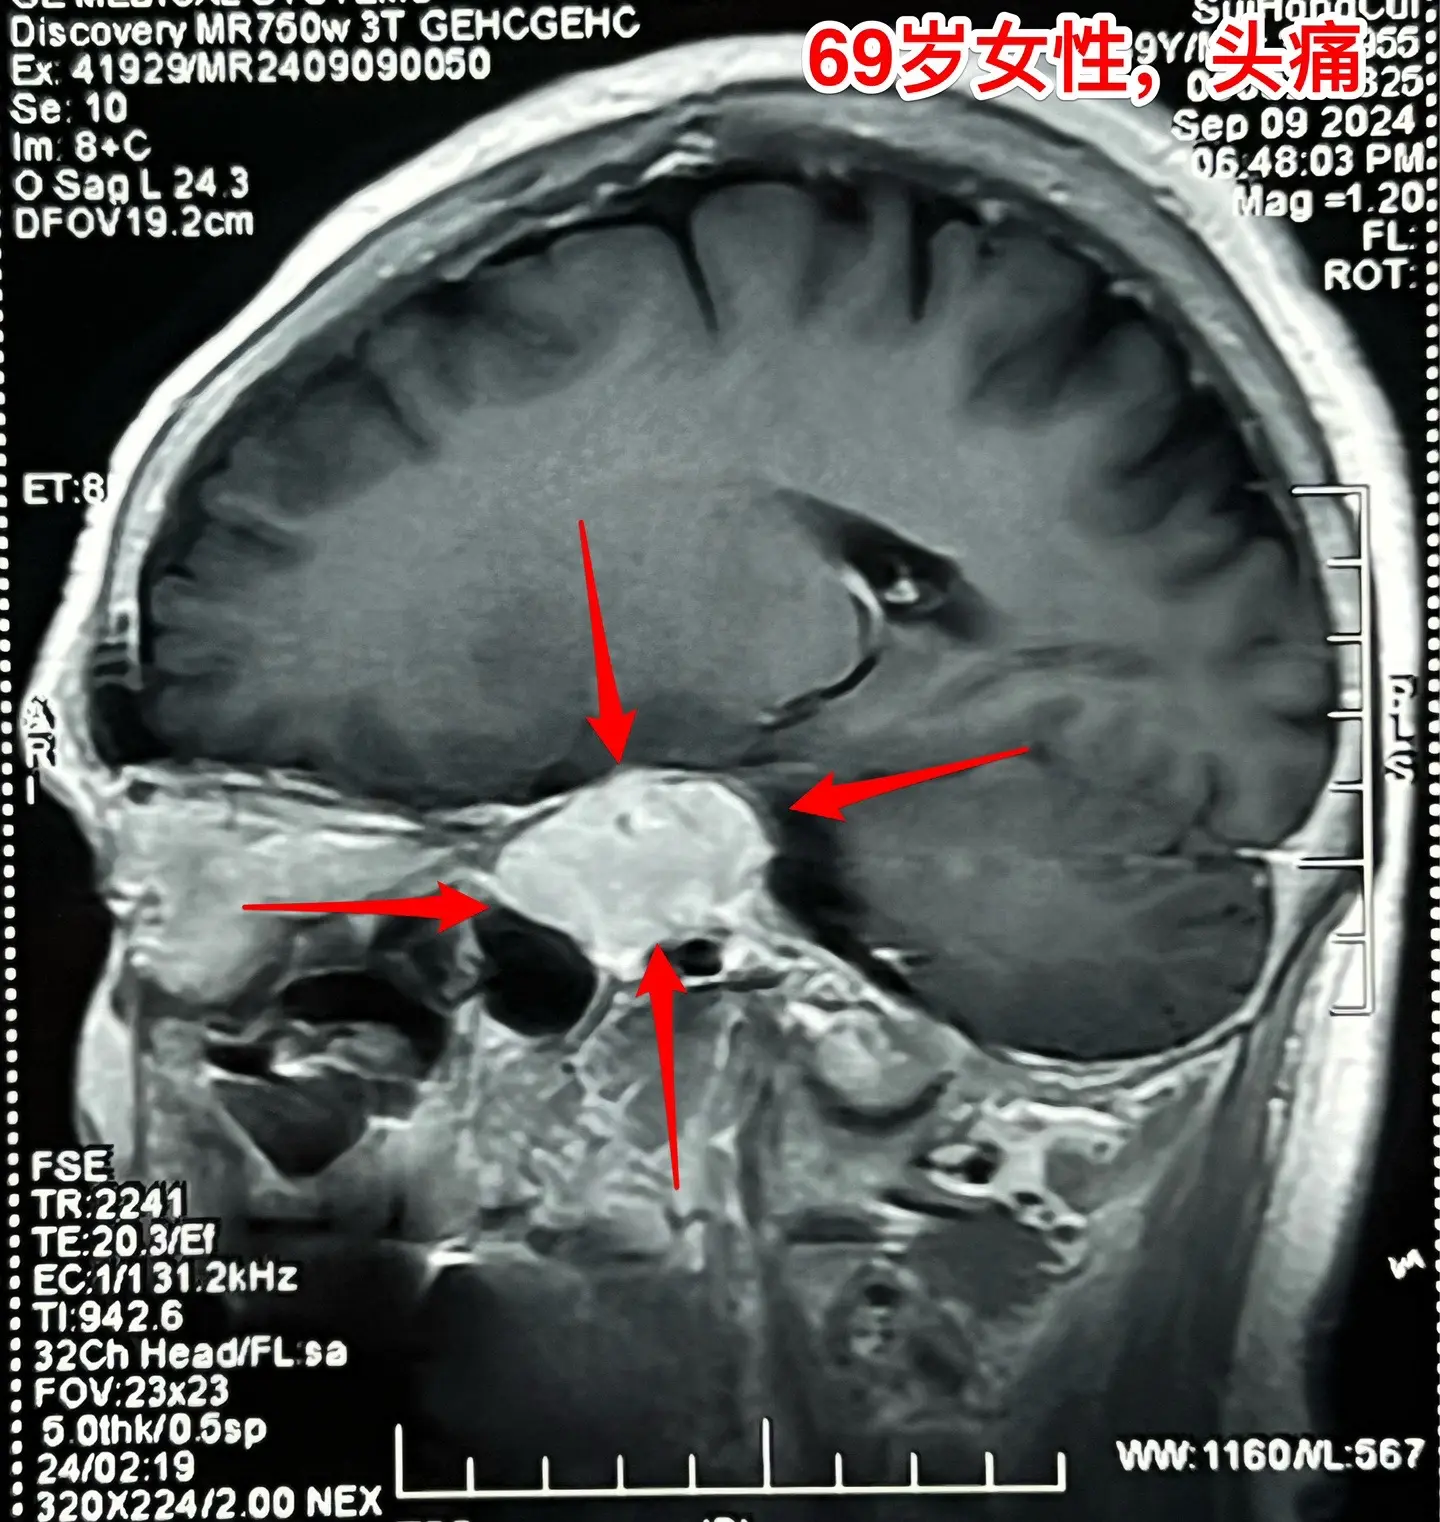

海绵窦区神经鞘瘤,是良性肿瘤。69岁青岛市老太太经常感到头痛,不太剧烈,没有专门去检查。九月份检查脑部磁共振发现左侧海绵窦长了肿瘤。在我院住院后作了强化磁共振,看见左侧海绵窦内有个大肿瘤,见图,考虑是神经鞘瘤,神经鞘瘤是良性肿瘤,如果完全切除了就可以治愈。 老太太有两个女儿,积极要求给她作手术。69岁年龄还是有点大,手术是有风险的! 9月12日下午四点开始进入手术室,手术持续到13日凌晨才结束。手术过程很顺利,肿瘤得到完全切除。今天看见老太太精神比较好,准备下地行走。神经鞘瘤海绵窦